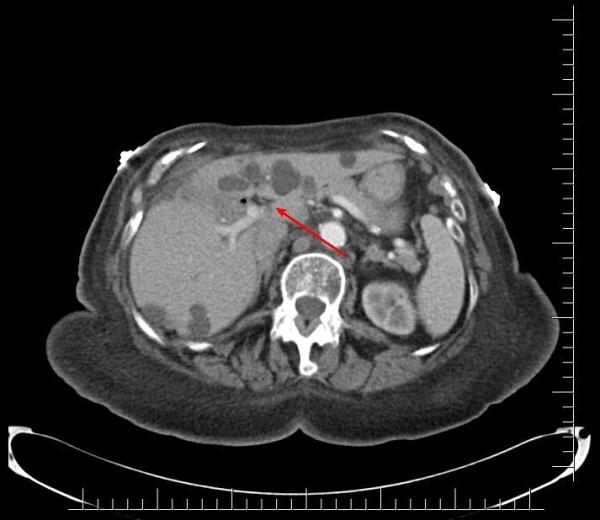

A 91-year-old African-American woman was referred to our out-patient gastroenterology clinic for evaluation of mild epigastric pain and intermittent melena. An abdominal computed tomography scan was remarkable for multiple hepatic cysts. Esophagogastroduodenoscopy revealed multiple blood clots at the ampulla of Vater. Endoscopic retrograde cholangiopancreatography showed a single 18 mm-sized filling defect in the common hepatic duct wall at the junction of the right and left hepatic duct, adjacent to one of the hepatic cysts. The ruptured hepatic cyst communicated to the bile ducts and was the cause of hemobilia with an atypical clinical presentation.

一名91岁的非裔美国女性因轻度上腹部疼痛和间歇性黑便被转诊至我们的门诊胃肠病诊所。腹部计算机断层扫描显示多个肝囊肿。食管胃十二指肠镜检查发现 Vater壶腹有多个血凝块。内镜逆行胰胆管造影显示在左右肝管交界处的肝总管壁上有一个18毫米大小的单一充盈缺损,与其中一个肝囊肿相邻。破裂的肝囊肿与胆管相通,是导致具有非典型临床表现的胆道出血的原因。